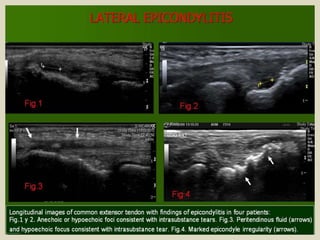

Lateral epicondylitis, also known as “tennis elbow” is an

overuse syndrome of the common extensor tendon. It is thought to

be due to repetitive micro trauma during supination of the forearm

and dorsiflexion of the wrist, that results in the breakdown of fibers

with tissue necrosis and fibrosis. Typically occurs in the 4th and 5th

decades, with equal prevalence in women and men. Patients

complain of poorly defined pain located over the lateral elbow that

is exacerbated with activities requiring wrist extension. Imaging is

reserved for cases which are refractory to conservative treatment,

to exclude other abnormalities and to assess the amount of

damaged tendon before surgery. US findings are: tendon thickening,

diffuse heterogeneity of the tendon with loss of the normal fibrillar

architecture, focal hypoechoic regions, intratendinous calcifications,

adjacent bone irregularity, enthesophytes at the tendon insertion

site, linear intrasubstance tears, peritendinous fluid and thickening

of peritendinous tissues and neovascularity in Colour Doppler

Epicondylitis. Longitudinal US image of the common extensor tendon old

woman depicts a linear hypoechoic region indicative of a partial-thickness

tear at the under-surface of the ECRB (arrowhead), with surrounding

heterogeneous echogenicity indicative of associated tendinosis (arrow).